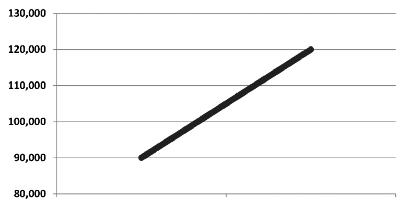

Aumento del numero dei decessi dovuti al cancro nei diversi gruppi di età, dal 1970 al 2000

Età dei pazienti 70 - 79 anni

Età dei pazienti 60 - 69 anni

Età dei pazienti 50 - 59 anni

Dati statistici per gli USA, dati comparabili per l’Europa. Fonte: Journal of the American Medical Association, 2005